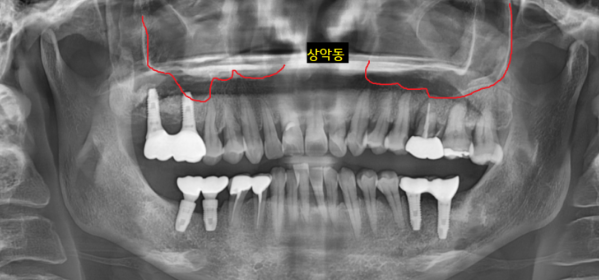

코 옆에 양쪽으로 동굴처럼 구멍이 있는데요.

상악동을 통해 공기가 드나들고

머리 무게를 줄여주는 기능을 하는 곳입니다.

이곳에 염증이 생기면 상악동염이라 한답니다.

ct에서 상악동까지 염증이 번진 게 확인됩니다.

어금니 염증이 상악동염을 유발했네요.

치아로부터 원인이 발생하였다고 하여

"치성 상악동염"이라 불립니다.